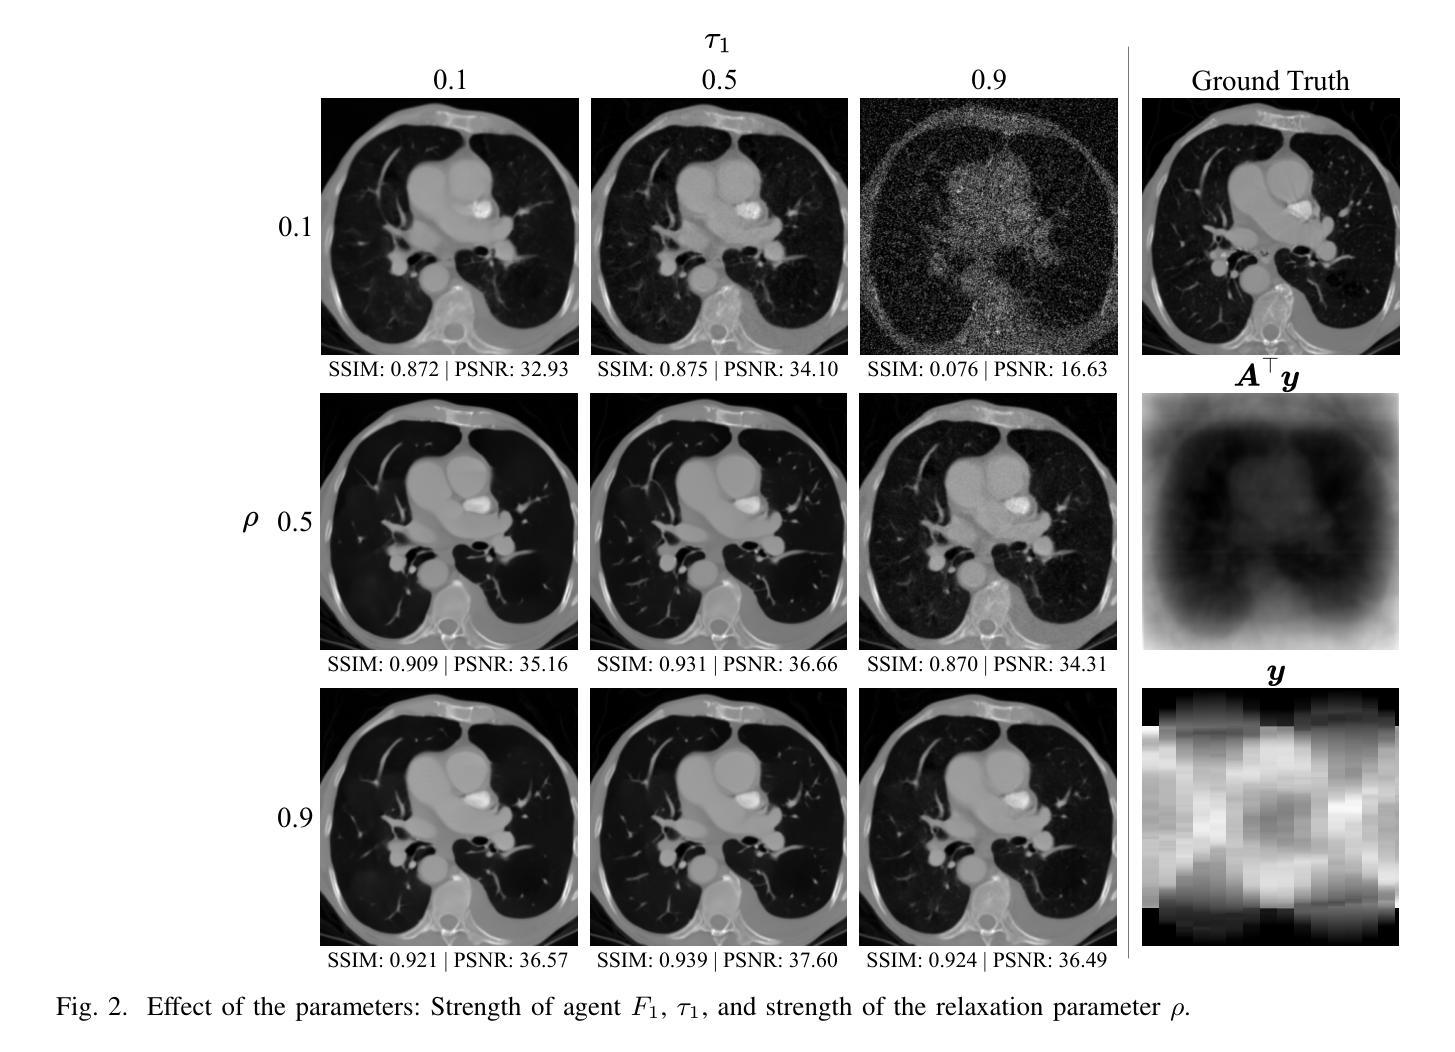

Sparse-view computed tomography (CT) reconstruction is fundamentally challenging due to undersampling, leading to an ill-posed inverse problem. Traditional iterative methods incorporate handcrafted or learned priors to regularize the solution but struggle to capture the complex structures present in medical images. In contrast, diffusion models (DMs) have recently emerged as powerful generative priors that can accurately model complex image distributions. In this work, we introduce Diffusion Consensus Equilibrium (DICE), a framework that integrates a two-agent consensus equilibrium into the sampling process of a DM. DICE alternates between: (i) a data-consistency agent, implemented through a proximal operator enforcing measurement consistency, and (ii) a prior agent, realized by a DM performing a clean image estimation at each sampling step. By balancing these two complementary agents iteratively, DICE effectively combines strong generative prior capabilities with measurement consistency. Experimental results show that DICE significantly outperforms state-of-the-art baselines in reconstructing high-quality CT images under uniform and non-uniform sparse-view settings of 15, 30, and 60 views (out of a total of 180), demonstrating both its effectiveness and robustness.

稀疏视图计算机断层扫描(CT)重建技术因其欠采样问题而面临根本性挑战,导致逆向问题表述不清晰。传统的迭代方法虽然通过引入手工制作或学习的先验来约束解的形式,但仍难以捕获医学影像中复杂的结构特征。与此不同,扩散模型(DMs)作为一种强大的生成先验模型,能够精确地模拟复杂的图像分布,最近开始崭露头角。在这项工作中,我们引入了扩散共识均衡(DICE)框架,该框架将双智能体共识均衡融入扩散模型的采样过程中。DICE交替进行以下操作:(i)数据一致性智能体,通过近端算子强制实施测量一致性;(ii)先验智能体,通过扩散模型在每个采样步骤中进行干净图像估计。通过平衡这两个互补智能体的迭代交互,DICE有效地结合了强大的生成先验能力和测量一致性。实验结果表明,在15、30和60个视图的均匀和非均匀稀疏视图设置下,DICE在重建高质量CT图像方面显著优于当前先进的基线方法,这证明了其有效性和稳健性。

基于扩散模型,我们提出了一个新的CT重建框架DICE。DICE结合了两种关键思想:通过近端操作器强制测量一致性的数据一致性代理和通过扩散模型进行清洁图像估计的先验代理。通过迭代平衡这两个互补的代理,DICE有效地结合了强大的先验能力和测量一致性。在均匀和非均匀稀疏视图条件下,DICE显著优于现有技术基线,在重建高质量CT图像方面表现出卓越的效果和稳健性。